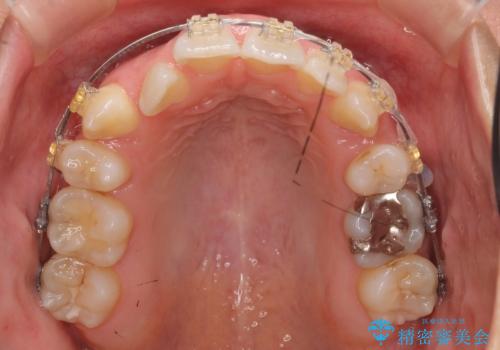

- 20代女性

- 矯正装置

- 審美装置

- 治療期間

- 2年3ヶ月

- 治療計画

- 前歯のがたつきと正中のずれを主訴に来院。

小臼歯を4本抜歯しています。